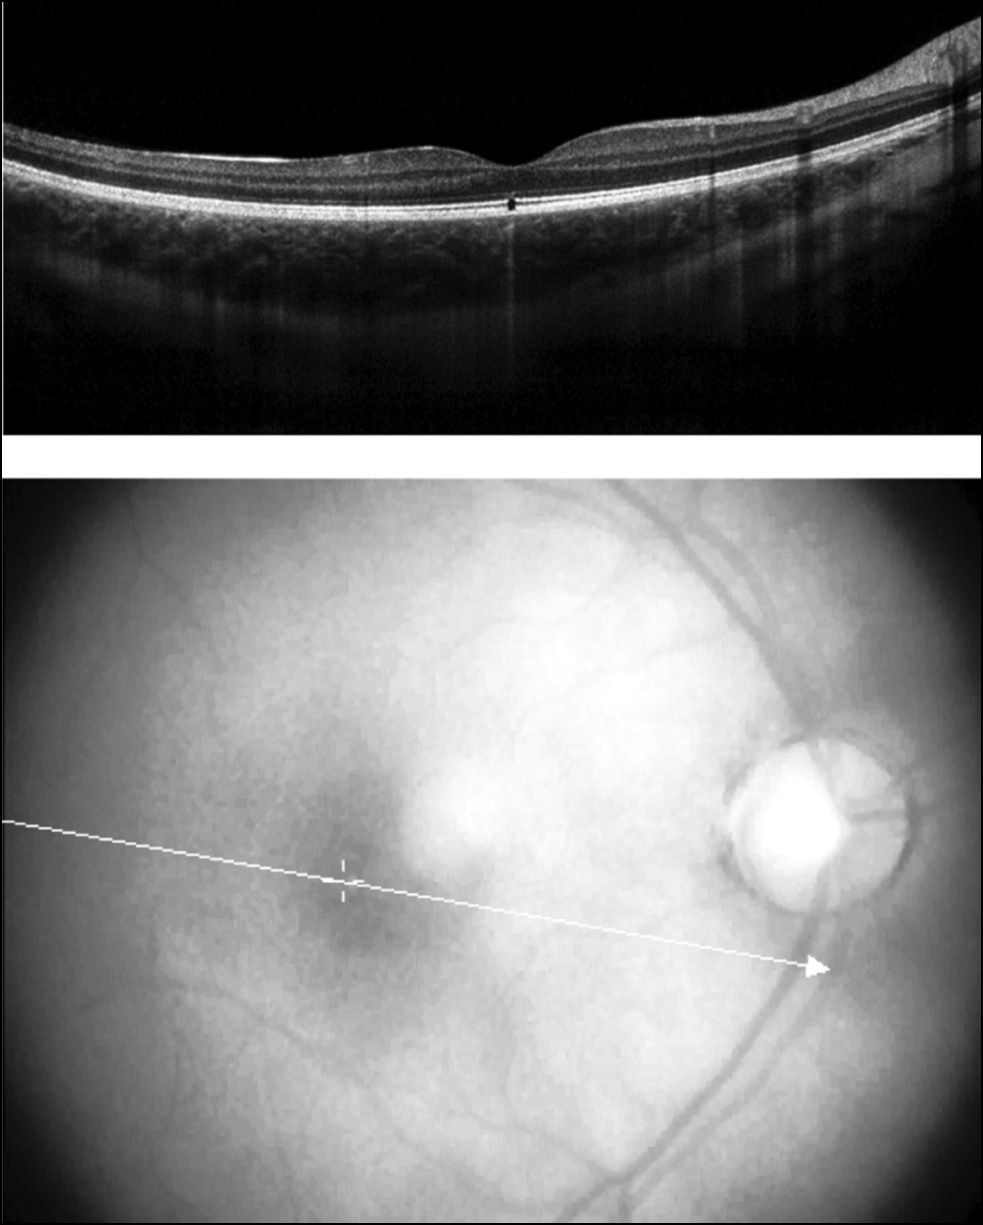

Случай 3. Мальчик 9 лет обратился с жалобами на появление тёмного «пятна» перед левым глаза после того, как год назад играл с лазерной указкой и светил ею себе в глаза. За медицинской помощью не обращался. При объективном обследовании установлено, что острота зрения правого глаза равна 1,0, левого — 0,5, не корригируется; оптические среды прозрачные. При офтальмоскопии в фовеа правого глаза выявлен точечный гипопигментированный очаг с чёткими границами, в макуле левого глаза — грубый проминирующий хорио-ретинальный очаг с пигментом. Для уточнения функции сетчатки и определения прогноза по зрению проведены электрофизиологические исследования. На правом глазу регистрировались нормальная смешанная и ритмическая ЭРГ, а на левом глазу показатели ритмической и макулярной ЭРГ были снижены, что отражало нарушение функциональной активности центральных отделов сетчатки. По данным ОКТ, на правом глазу выявлен точечный дефект пигментного эпителия в фовеа (рис. 3), а на левом глазу — разрушение пигментного эпителия и формирование субретинальной неоваскулярной мембраны (СНМ). Выявленные изменения коррелировали с остротой зрения и показателями ЭРГ и определяли благоприятный прогноз по зрению на правом глазу, но серьёзный — на левом.

Рис. 3. Данные ОКТ: повреждение пигментного эпителия и зоны контакта сетчатки в проекции фовеа.

Fig. 3. OCT data: destruction of the pigment epithelium and the retinal contact zone in the fovea projection.

Случай 4. Мальчик 15 лет обратился в центр с жалобами на снижение зрения на обоих глазах. Из анамнеза известно, что два месяца назад светил себе в глаза лазерной указкой, время экспозиции составило около 1 минуты на каждый глаз. Через два дня снизилось зрение левого глаза. Пациент был госпитализирован в многопрофильное педиатрическое медицинское учреждение г. Москвы с диагнозом «лучевой ожог макулярной области обоих глаз». В стационаре получал местную противовоспалительную терапию. При выписке из стационара острота зрения правого глаза была 0,9–1,0, левого — 0,1, не корригировалась. Через 3 недели после выписки острота зрения снизилось на обоих глазах, пациент был повторно госпитализирован в педиатрическое медицинское учреждение г. Москвы с диагнозом «последствия лучевого ожога макулярной зоны обоих глаз, центральная хориоретинальная дистрофия сетчатки обоих глаз, осложненная СНМ на правом глазу». Получал противовоспалительную и дегидратационную терапию. Через 3 недели после выписки из стационара при обследовании в Центре острота зрения правого глаза была 0,05, не корригировалась; левого глаза — 0,1, эксцентрично, не корригировалась. Оптические среды были прозрачными. При офтальмоскопии на правом глазу в макуле выявлен проминирующий очаг с перифокальным отёком прилежащей сетчатки, с элементами интраретинального кровоизлияния; на левом глазу в макуле определялся атрофический рубцовый очаг белого цвета, с чёткими границами, окружённый зоной гипопигментации.

На ОКТ справа было получено «классическая картина» активной хориоидальной неоваскулярной мембраны с дефектом пигментного эпителия и активными новообразованными сосудами, которые приподнимают все слои нейроэпителия и изменяют структуру и расположение фовеа (рис. 4). На левом глазу выявлен дефект элипсоидной зоны и зоны фоторецепторов с частичным поражением пигментного эпителия (рис. 5).

Рис. 4. Данные ОКТ: разрушение пигментного эпителия сетчатки и формирование хориоидальной неоваскулярной мембраны.

Fig. 4. OCT data: destruction of retinal pigment epithelium and formation of choroidal neovascular membrane.

Рис. 5. Данные ОКТ: повреждение слоя контакта и частично слоя пигментного эпителия с формированием «кистовидного» дефекта.

Fig. 5. OCT: damage of the contact layer and particually of the pigment epithelium layer with the formation of a defect.